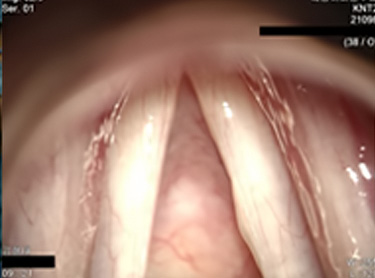

수술 1년 후 성대